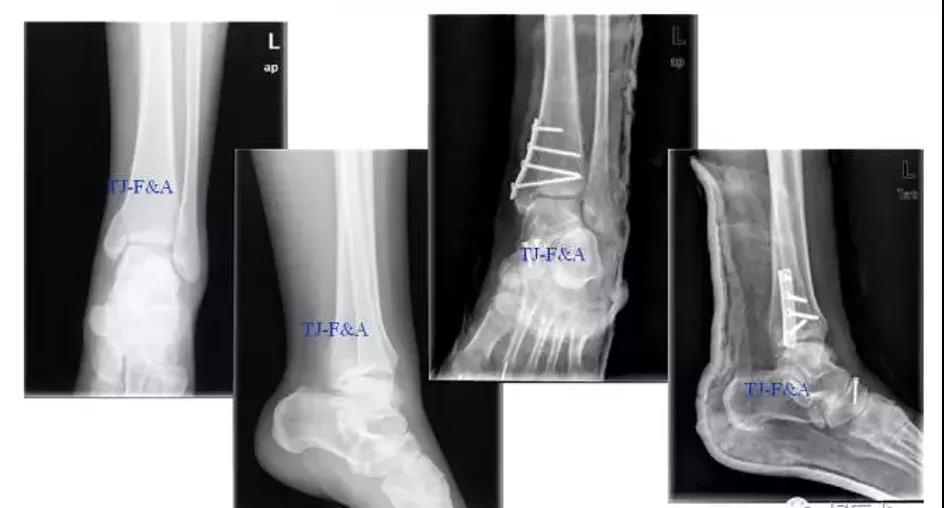

术前DR